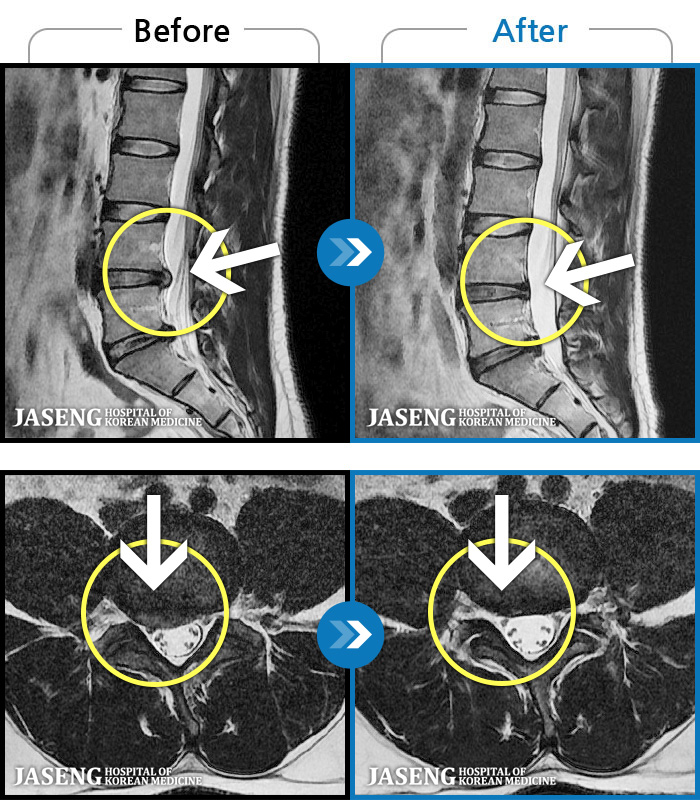

MRI ġ

MRI ũ ʸ Ȯϼ.

Ƹ ϰ ־.